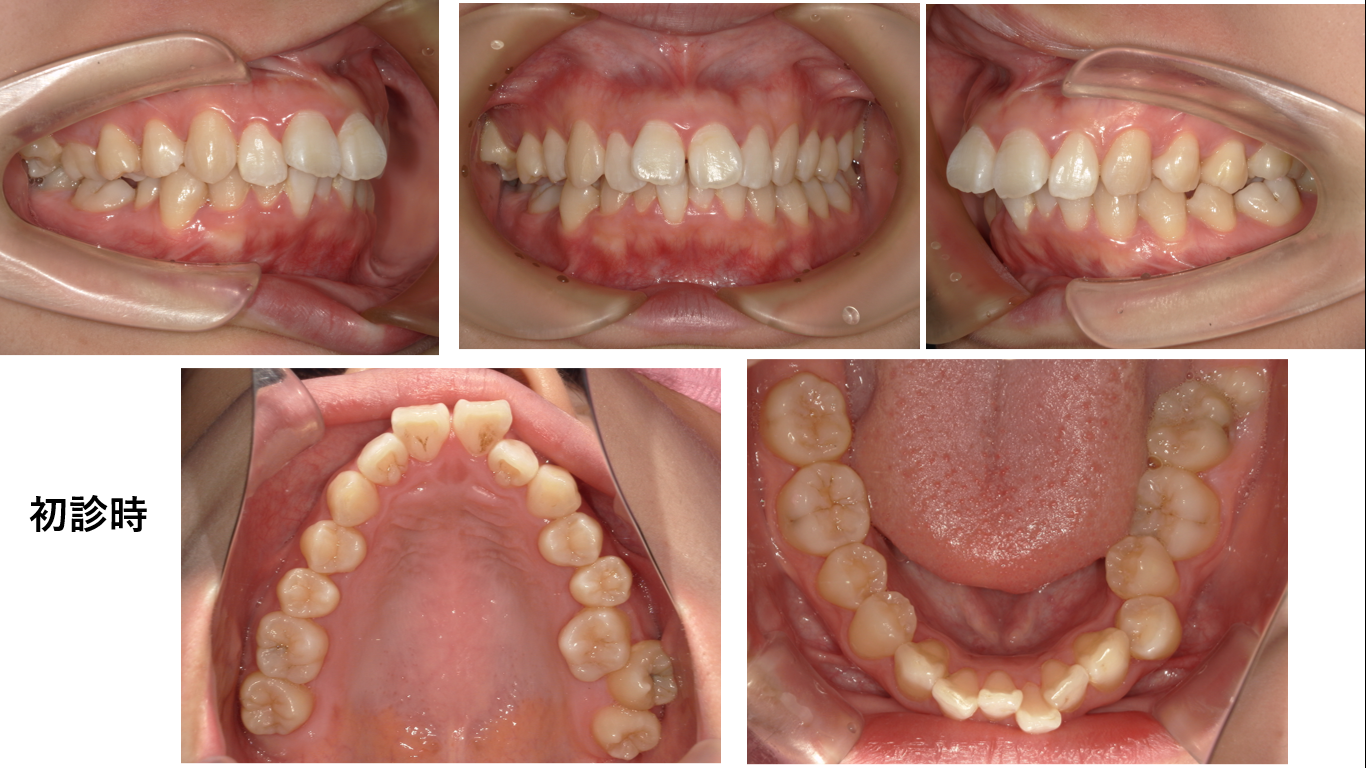

矯正症例147 AngleⅠ級 上顎前突 裏側矯正 舌側矯正

初診時23歳6か月、抜歯部位:上顎左右4番、上下顎左右8番、治療期間3年 治療費総額¥1,560,000(税込み)